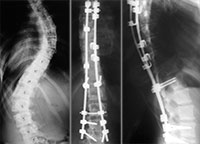

Дарье 15 лет, она из Обнинска. Её диагноз – идиопатический комбинированный сколиоз 4 степени. В Государственном бюджетном учреждении здравоохранения «Калужская областная детская больница» ей по медицинским показаниям планируют установить имплантаты стабилизации позвоночника Medtronic (США). Оплата имплантатов за счет бюджетных средств не производится. Стоимость базовой комплектации имплантатов и расходных материалов составляет 670 020 рублей.

Главный врач Калужской областной детской больницы В.М.Михайлов обратился с просьбой о помощи в обеспечении операции по установке имплантатов стабилизации позвоночникаMedtronic (США). Стоимость проведения операции, необходимого медикаментозного обеспечения и последующей реабилитации оплачивается за счет бюджетных средств. К сожалению, бюджетом не оплачивается стоимость имплантатов, поэтому Дарья будет прооперирована только при условии привлечения необходимых благотворительных пожертвований.